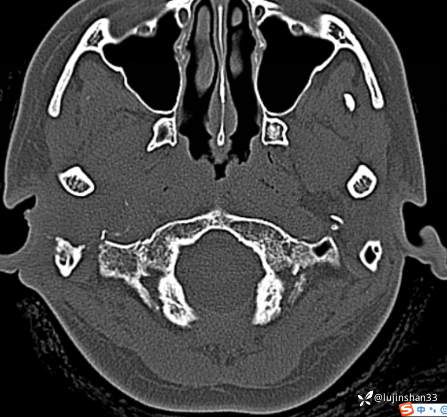

颞骨CT: